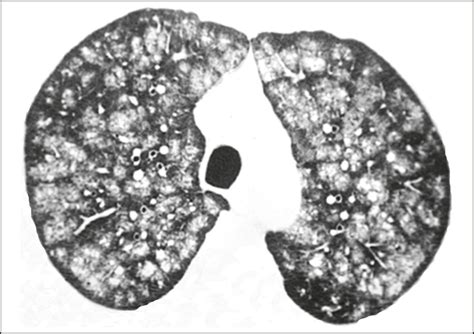

Diagnosing calcification in lungs involves a combination of medical history, physical examination, and diagnostic tests. Some of the common diagnostic methods include:

• CT Scan: A computed tomography (CT) scan provides detailed images of the lungs and can help identify the location and extent of the calcification.